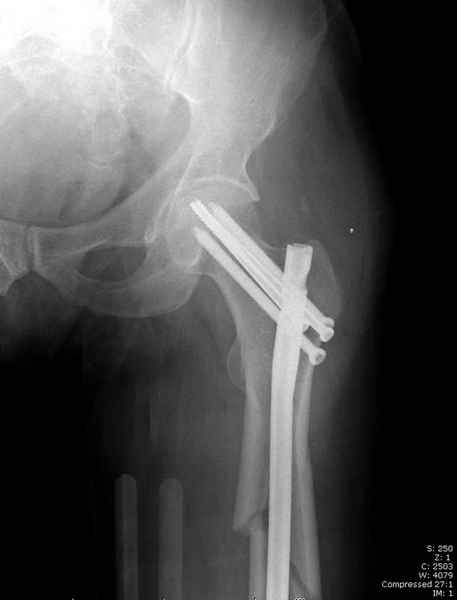

Учитывая, что случай ургентный, больной поступил вечером, не стали делать вытяжение и срочно провели операцию по фиксации перелома бедра антеградным штифтом Versa Nail от DePuy.

Для профилактики дальнейшего раскола в шейке предварительно во время проксимального рассверливания спереди и сзади провели временные спицы, которые в дальнейшем были заменены на шурупы (miss nail method)

Обычная спасательная фасциотомия для обычного больного в этом случае было бы приговором, поэтому несмотря на высокие цифры компартментального мониторинга больного оставили под наблюдением с обкладкой конечности льдом.

Кровотечение удалось контролировать, и больной через пару дней выписан на амбулаторное лечение.